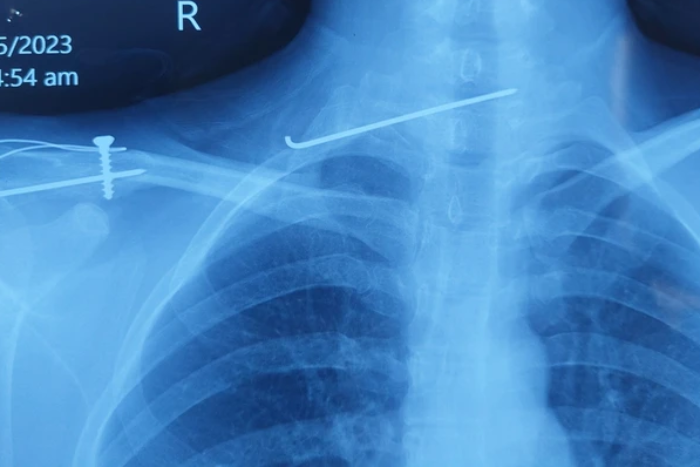

Bệnh nhân phẫu thuật cố định xương đòn bằng đinh từ 3 năm trước nhưng không kiểm tra theo quy trình của bác sĩ, chiếc đinh đã trôi vào cột sống cổ.